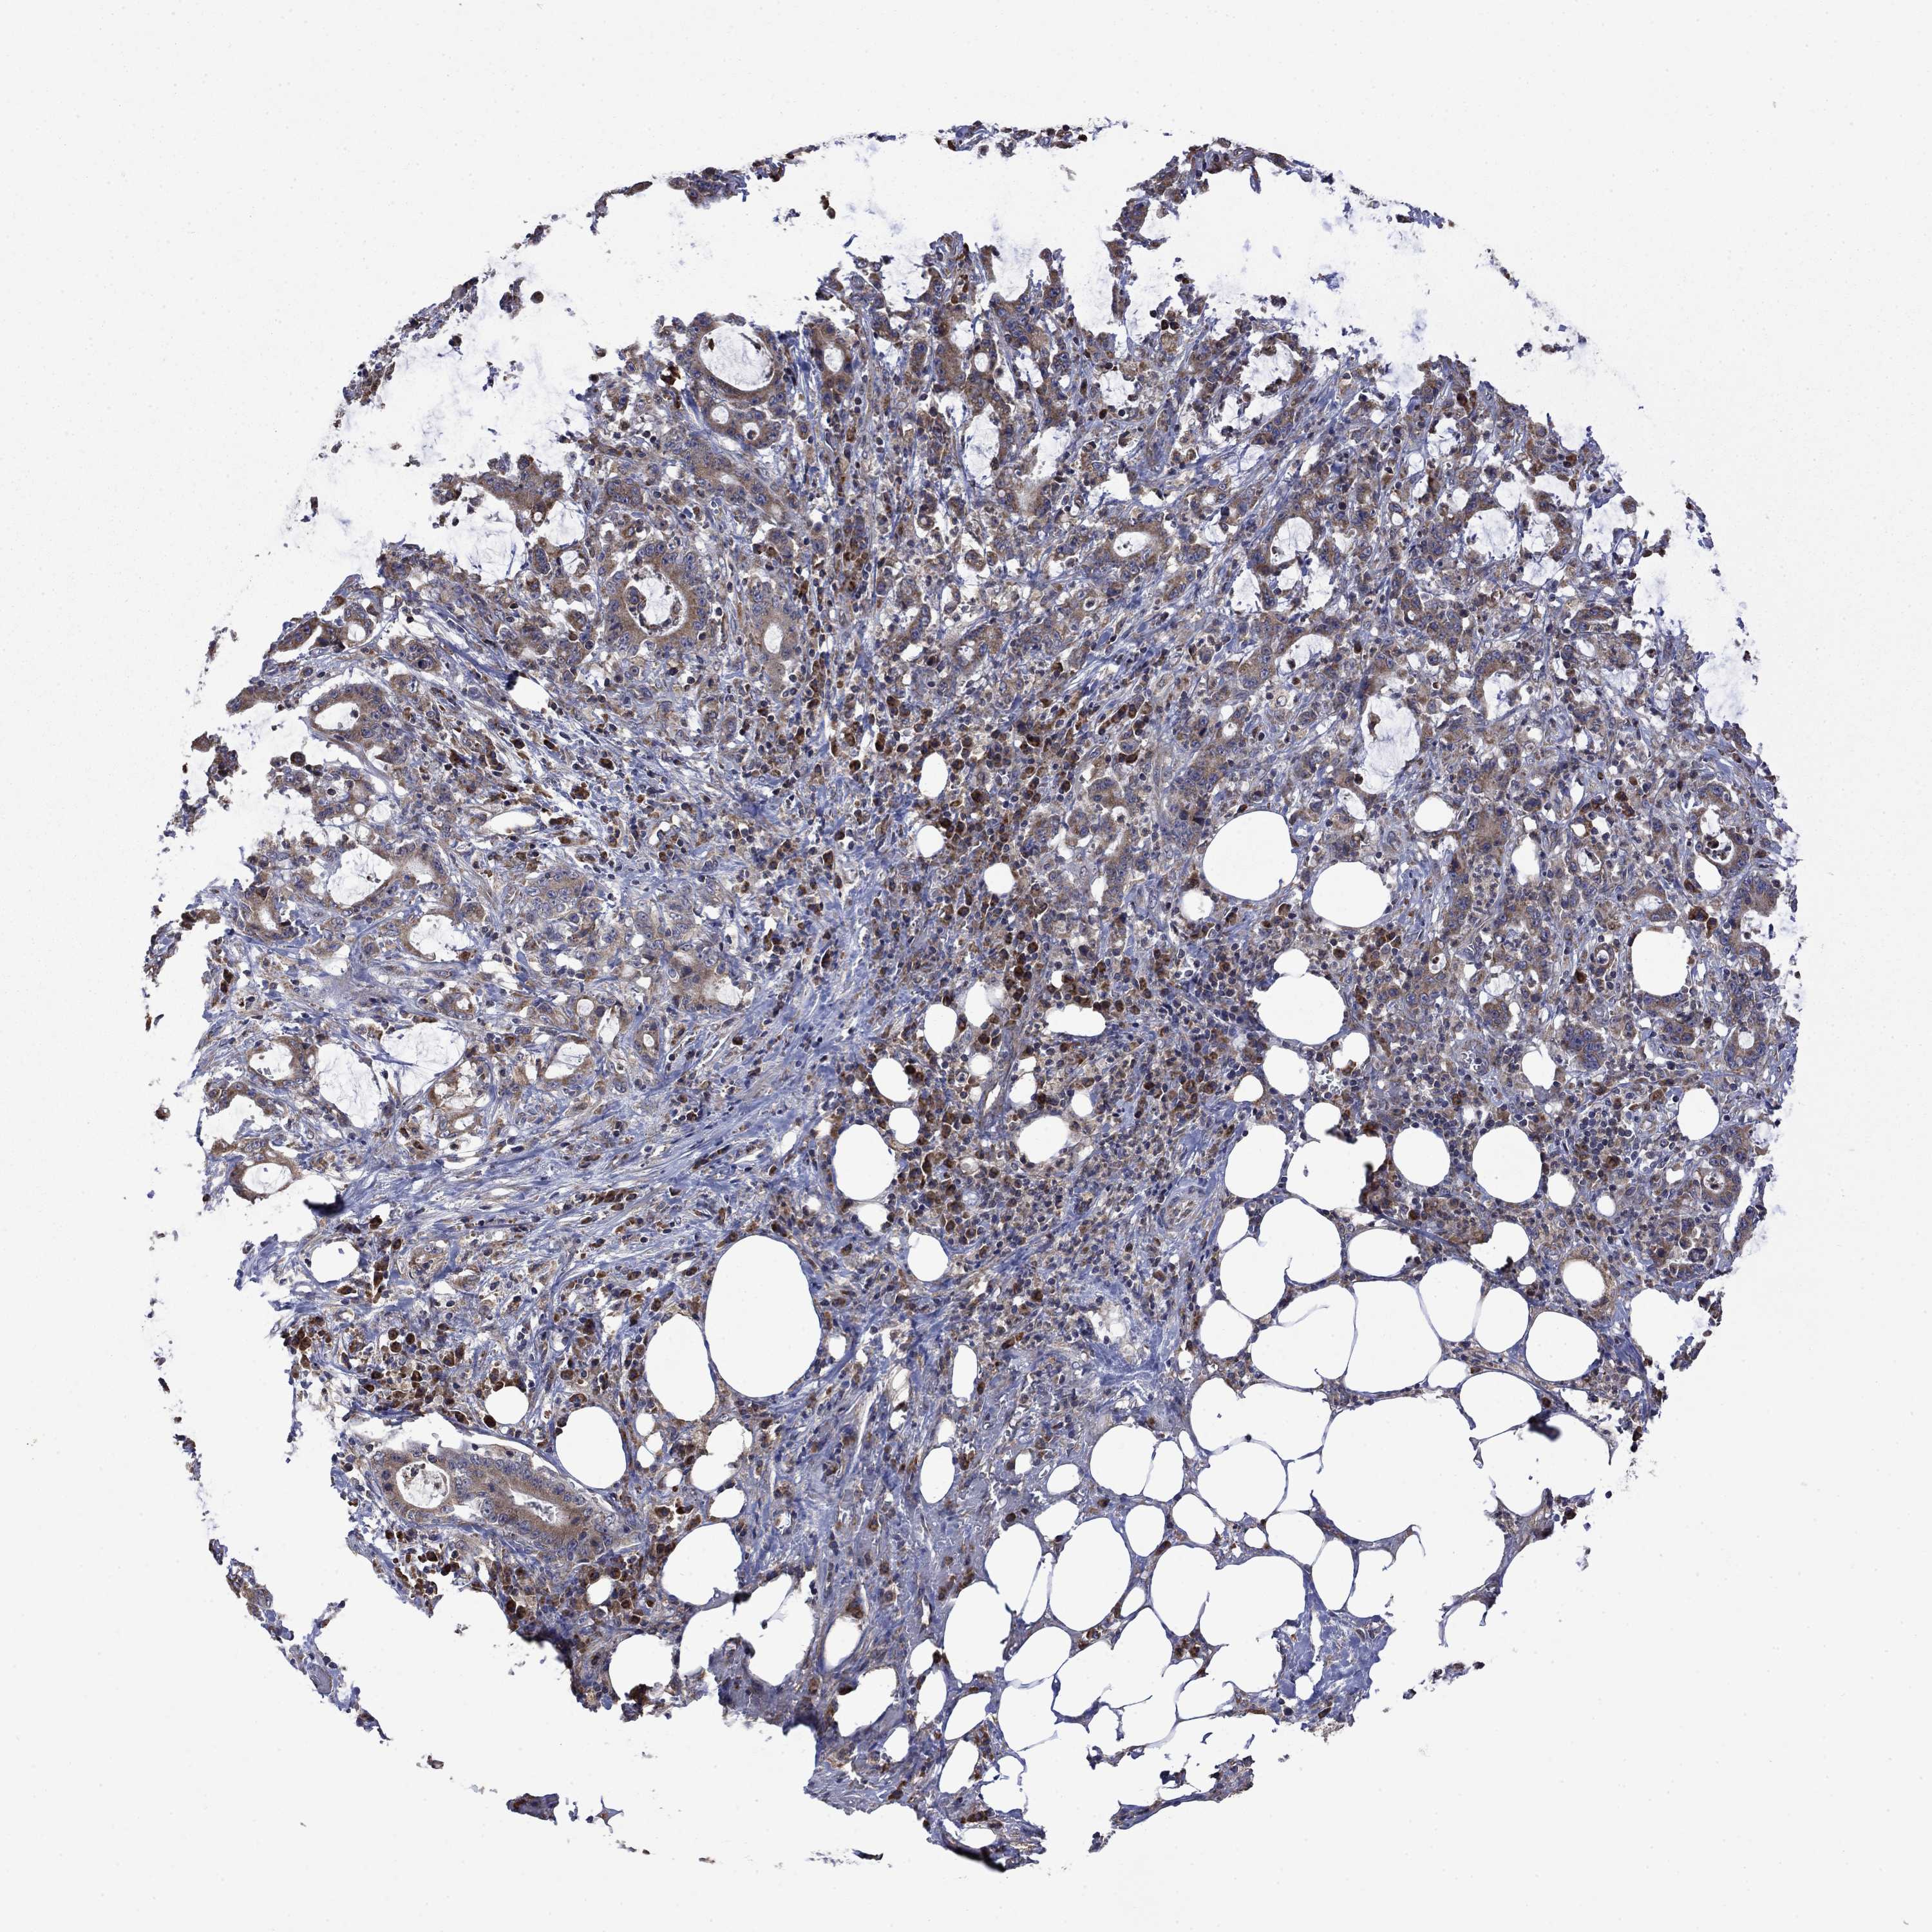

STOMACH CANCER - Protein expressioni

A mouse-over function shows sample information and annotation data. Click on an image to view it in a full screen mode. Samples can be filtered based on level of antibody staining by selecting one or several of the following categories: high, medium, low and not detected. The assay and annotation is described here.

Note that samples used for immunohistochemistry by the Human Protein Atlas do not correspond to samples in the TCGA dataset.

Antibody stainingi

Antibody staining in the annotated cell types in the current human tissue is reported as not detected, low, medium, or high, based on conventional immunohistochemistry profiling in selected tissues. This score is based on the combination of the staining intensity and fraction of stained cells.

Each image is clickable and will lead to virtual microscopy that enables deeper exploration of all samples and also displays staining intensity scores, fraction scores and subcellular localization as well as patient and tissue information for each sample.

Antibody HPA067869

Antibody CAB009499

Staining

High

Medium

Low

Not detected

Intensity

Strong

Moderate

Weak

Negative

Quantity

>75%

75%-25%

<25%

None

Location

Nuclear

Cytoplasmic/membranous

Cytoplasmic/membranous,nuclear

Adenocarcinoma, NOS

Adenocarcinoma, High grade